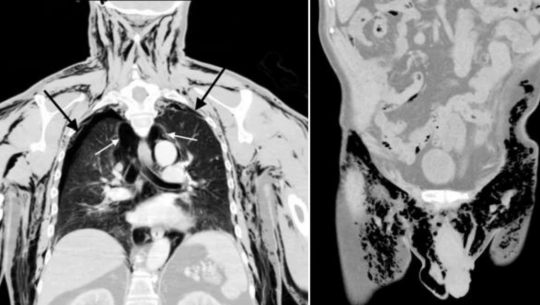

पुरुषको लिङ्गबाट अचानक सिट्ठी बजेपछि...

एजेन्सीः अमेरिकामा एक पुरुषले असामान्य स्वास्थ्य अवस्था भोग्नुपरेको छ। ती पुरुषको लिङ्गबाट अचानक सिट्ठी बजेको छ।... विस्तृतमा